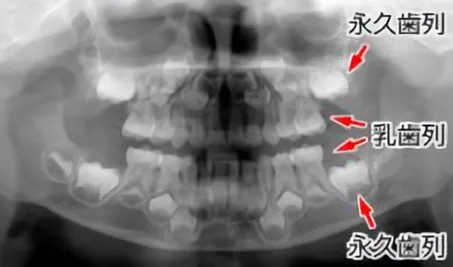

【5才児の乳歯から永久歯へ、交換過程のレントゲン像】

◆乳歯列

きれいな並びをしています。

◆乳歯の根の吸収がまだおこっていません。

永久歯列

永久歯の生える順に従って、歯の頭が出来ています。